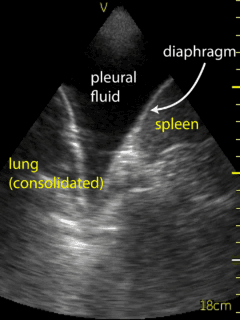

Ultrasound of the lung bases was conducted to assess for effusion by the consultant Respirologist using a Vscan device. There was no fluid present in the patient’s right pleural space. A moderate sized pleural effusion (Figure 1) was seen on the left side. The ultrasound of the left lung based was used to guide the thoracentesis (Video 1). The site of catheter insertion was landmarked at the 8th intercostal space, roughly 10 cm from the spine. Lidocaine was used to anesthetize down to the pleura. The catheter was introduced along the same location and angle, and a total 1.5 litres of serosanguinous fluid was collected. The procedure was well tolerated without complications.  Ultrasound following the procedure showed a very small amount of remaining fluid. Sliding lung/pleura could be seen as well. The patient experienced relief of symptoms following the procedure.